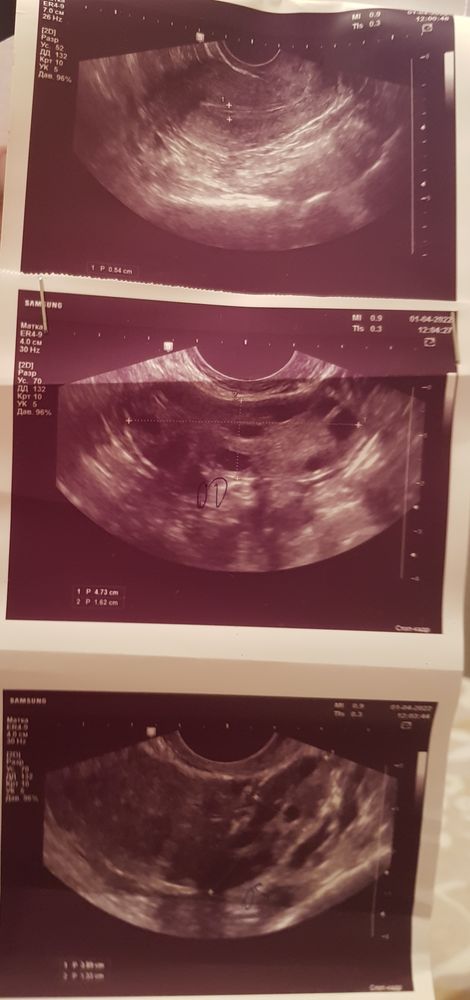

На 1ой ФМ врач сказала, что в правом яичнике видит ЖТ (11 ДЦ), а в левом ДФ 15 мм.

На 2ой ФМ так же ЖТ в правом (14 ДЦ), но в левом уже не видит ДМ...

При всём при том про ЖТ нигде в заключении не сказано. Последний цикл был 35 дней, до этого менструации нормальной не было (СПКЯ).

Я бы сходила к другому узисту и желательно в другую клинику🤔Как так можно забыть указать жт и кровоток..Эндометрий хороший у вас